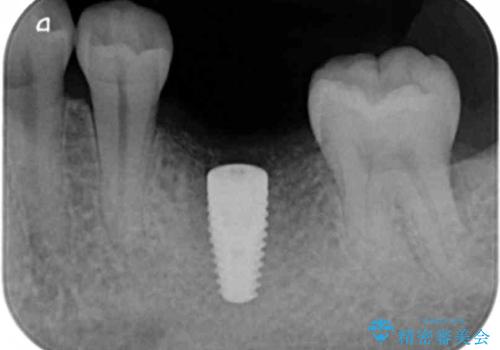

- 46.2万円(仮歯・ストローマンインプラント・チタンカスタムアバットメント・ジルコニアクラウン)費用は治療当時の料金となります

減ってしまった顎骨に増骨処置を行うことで、より安定した環境で長く使用できるようなインプラント治療を行っています。